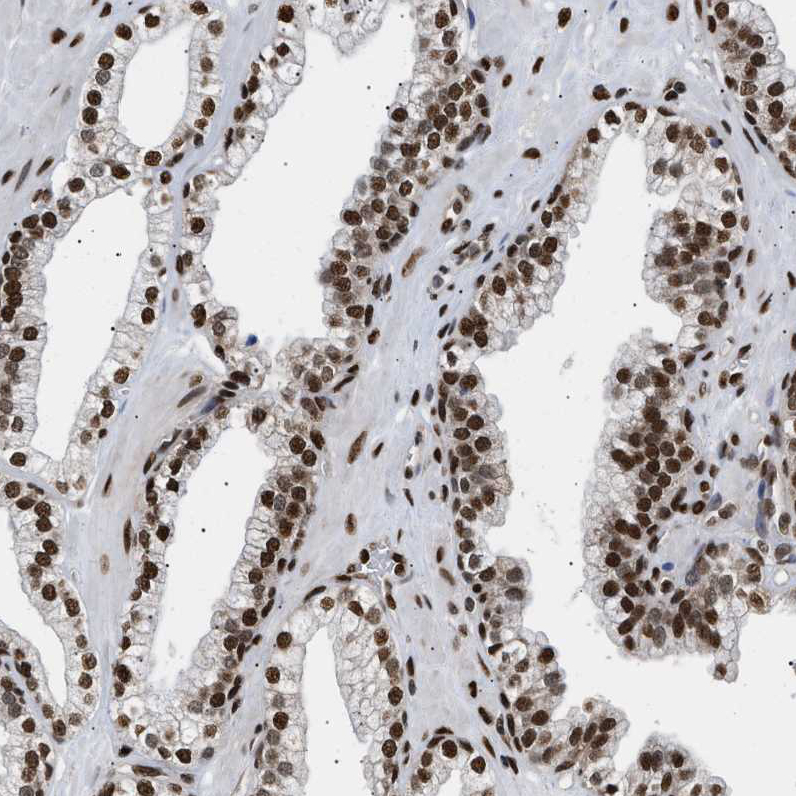

Immunohistochemical staining of human cerebral cortex shows strong nuclear positivity in neuronal cells.